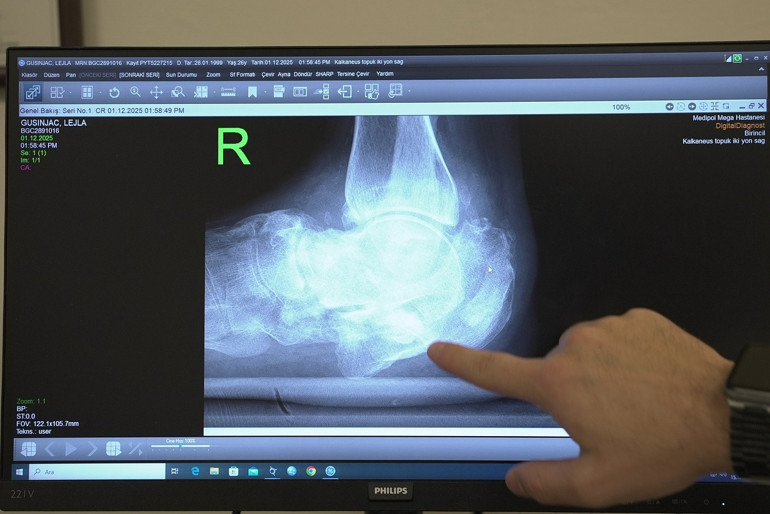

Diyabetle gelen sağlık sorunlarına değinen Doç. Dr. Çatal, “Hastamız 26 yaşında ve uzun yıllardır kontrolsüz diyabeti bulunuyor. Diyabet hastalarında ayaklarda his kaybı oluşabiliyor. Bu nedenle küçük bir kırık bile fark edilmeden ilerleyerek ciddi deformasyonlara yol açabiliyor. Hastamızda topuk kemiğinde, yani kalkaneus dediğimiz kemikte ciddi bir kırık gelişmiş. Üzerine basmaya devam ettikçe ayağında genişleme oluşmuş. Ameliyatta topuk kemiğini yeniden yapılandırdık. Kalça kemiğinden aldığımız kemik greftleriyle bir ‘kurtarma cerrahisi’ uyguladık. Amacımız, hastanın ağrısız ve düzgün basabileceği, normale en yakın anatomiyi sağlamaktı. Bu hedefe ulaştık.” diye konuştu.